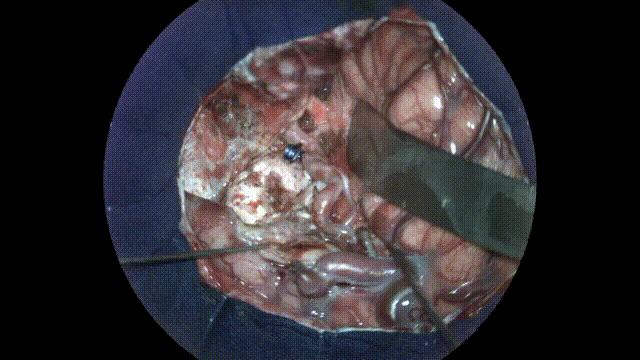

AVM首次評估

圖8:打開硬腦膜后,顳葉上明顯可見AVM,也使用增強現實熒光進行了評估。

視頻1:使用增強現實熒光進行AVM首次評估。外科醫(yī)師能夠在立體視圖下進行操作和探索,同時評估血流。

增強現實熒光有助于了解AVM的表面形態(tài),并確認之前決定的手術策略。